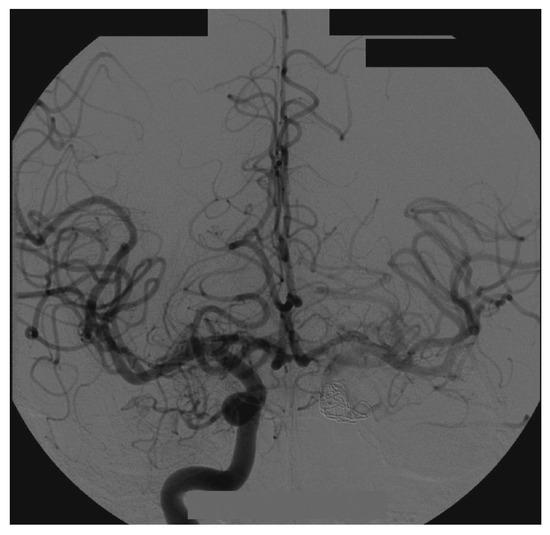

Figure 7.

Right side angiography, with coronal and normal views.